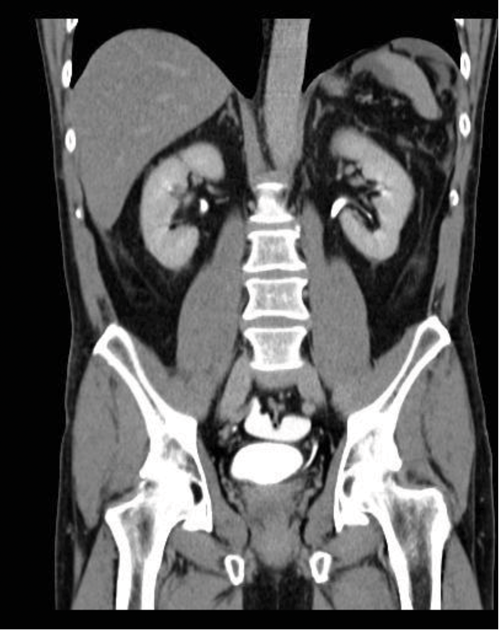

Case 4

A 52-year-old male was admitted following a fall.

1. How has the CT been performed?

2. Describe the findings.

3. What is the diagnosis?

4. What management is usually required?

- A CT urogram has been undertaken with contrast seen in both collecting systems. A CT cystogram was performed at the same time, with contrast instilled into the urinary bladder via existing Foley catheter. This allows assessment of both the upper tracts and the bladder to look for any injury following trauma. Contrast should be used at a concentration of 10% during CT cystogram, otherwise the contrast opacification will be too dense and make interpretation difficult.

- There is abnormal contrast opacification seen superiorly to the urinary bladder, within the peritoneal cavity.

- Findings are in keeping with an intraperitoneal bladder rupture. This is seen in approximately 15% of major bladder injuries and is usually caused by direct trauma to a distended bladder. The axial CT image demonstrates fluid, some of which has opacified with contrast, in the peritoneum.

- Surgical repair is required for intraperiteonal bladder rupture. Extraperitoneal bladder rupture is more common, accounting for 80-90% of cases, and is usually due to penetrating trauma or as a result of pelvic fractures. Treatment of an extraperitoneal bladder rupture is conservative, with a Foley catheter left in situ until the rupture heals.